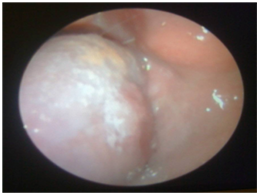

A 71 year old female patient with history of chronic smoking, type 2 diabetes mellitus and arterial hypertension, presented with a white nodular painful mass on the left lateral side of the tongue of one month of duration. She had been treated with mouth washes, antibiotics and antimycotics with no improvement. Two weeks later she noticed aslow-growing, non-painful tumoron the left side of the neck. Physical examination revealed limitation of the oral opening dueto pain and a very painful tumor on the Left part of the Tongue fixed to the floor of the mouth (Figure 1). On the neck an enlarged thyroid was palpated with predominance of the left lobe and a second level node of 3cm, indurated and fixed to the under lyingt issue. Three weeks after the primary evaluation, she presented with increased volume of the tongue tumor, involving submental region and both submandibular triangles with predominance of the left one. Computed tomography showed an hypodense tumor on the left side of the tongue, heterogenouse lymph node on the second left level of the neck and a hypodense mass in the left lobe of the thyroid with calcifications on the inside. She was admitted for an incisional biopsy of the tongue tumor, and fine-needle aspiration cytology (FNAC) of the node and thyroid tumor (Figure 2). Histopathologic report was a primary anaplastic thyroid carcinoma with tongue and neck metastases (Figure 3). The patient was sent to the National Cancer Institute of Mexico, where they only offered palliative care because she rejected any other therapeutic measures.

Figure 1 Left part of the tongue fixed to the floor of the mouth.